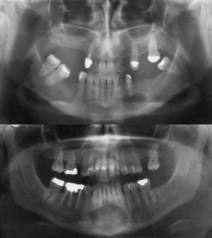

Radigráficas

Se aprecian áreas radiolúcidas situadas con más frecuencia en el ápice de los dientes. Su tamaño es variable. Suelen tener bordes bien definidos y ser de forma oval o redondeada. Es prácticamente imposible distinguir entre un granuloma periapical y un quiste, radiográficamente.